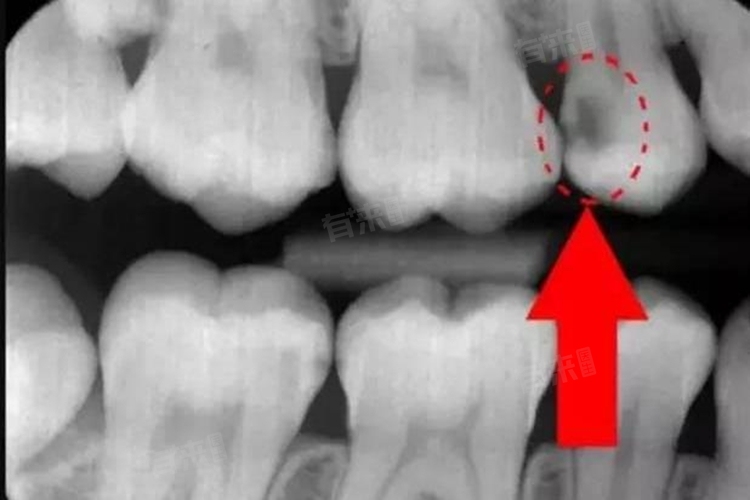

- 龋齿是一种常见的口腔疾病,主要是由于细菌侵蚀牙齿硬组织而引起的,在早期龋齿可能只表现为牙齿表面的轻微变色或小的龋洞,此时仅凭肉眼观察可能难以发现。而拍牙片可以提供更详细的牙齿内部结构信息,帮助医生发现潜在的龋齿问题。

- 一般来说常用的牙片有小牙片、全景片和锥形束CT也就是CBCT等,小牙片主要用于观察单个牙齿或局部区域的情况,可以清晰地显示牙齿的冠部和根部,对于早期龋齿的发现有一定的帮助。全景片则可以展示全口牙齿的情况,包括牙齿的排列、牙槽骨的状态等,对于发现多颗牙齿的龋齿以及评估龋齿对周围组织的影响有重要意义。CBCT具有更高的分辨率,可以提供三维的牙齿图像,对于复杂的龋齿病例,如龋齿接近牙髓或根尖周病变时,能够更准确地判断龋齿的范围和程度。

- 但是拍牙片也不是万能的,对于非常早期的龋齿,尤其是在牙釉质层的浅龋,牙片可能无法清晰显示。是因为早期龋齿的病变范围较小,牙齿硬组织的密度变化不明显,在牙片中可能难以与正常的牙齿结构区分开来。拍摄牙片的质量也会影响龋齿的检出率,如果牙片曝光不足、图像模糊或者存在伪影等问题,可能会导致龋齿被漏诊。